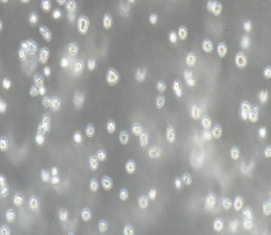

- 细胞形态:

悬浮生长

2)形态:悬浮